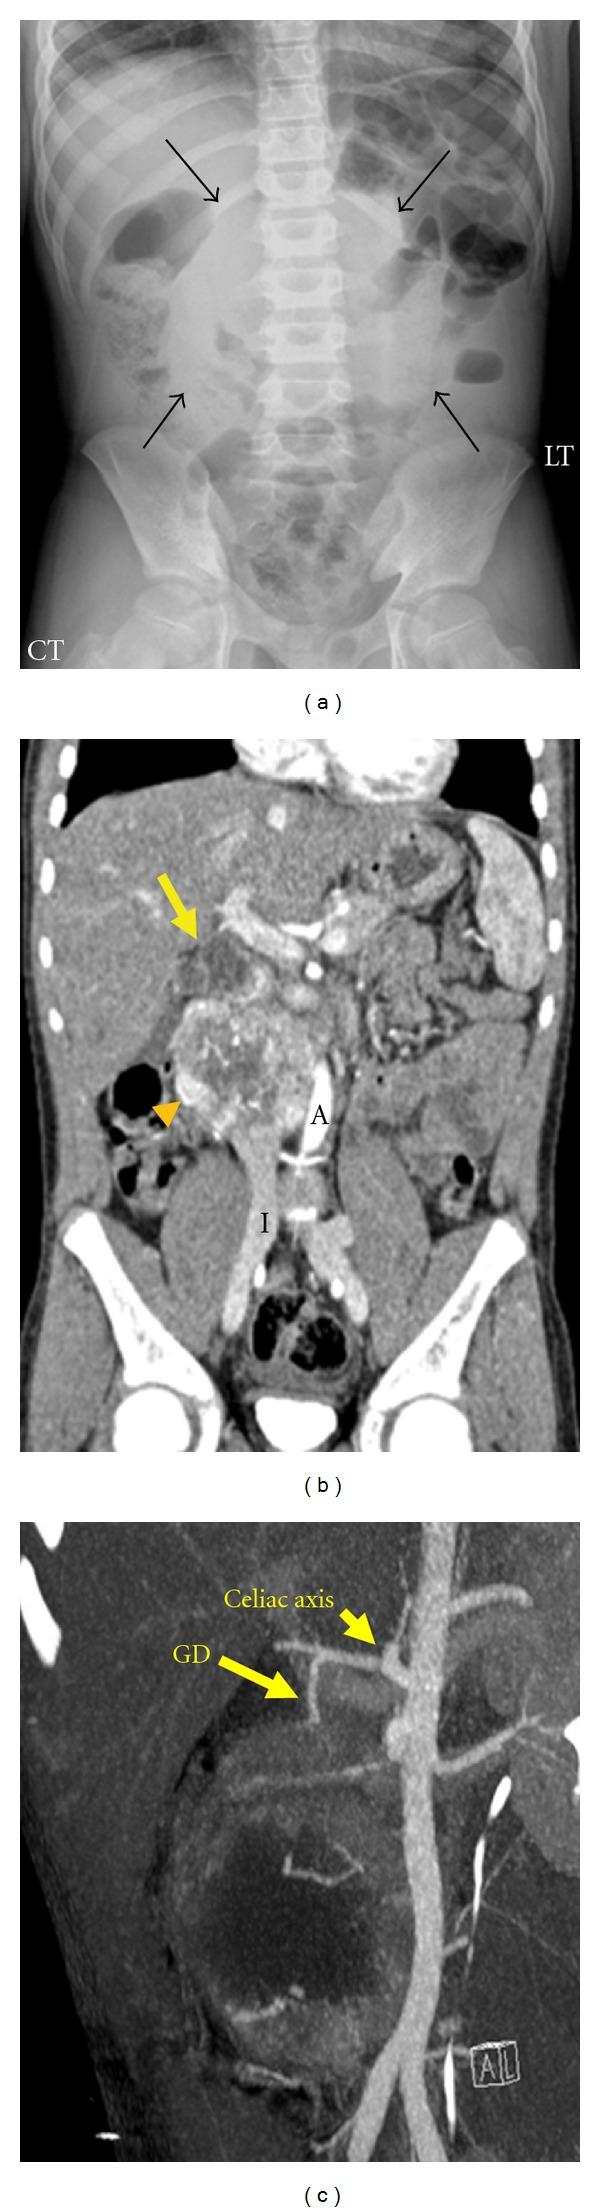

A 10-year-old boy presented with a 3-day history of worsening abdominal pain, fever, emesis and melena. Abdominal ultrasound revealed a right upper quadrant mass that was confirmed by computed tomography angiogram (CTA), which showed an 8 cm well-defined retroperitoneal vascular mass. (123)Iodine metaiodobenzylguanidine ((123)MIBG) scan indicated uptake only in the abdominal mass. Subsequent biopsy revealed a paraganglioma that was treated with chemotherapy. This case represents an unusual presentation of a paraganglioma associated with gastrointestinal (GI) bleeding and highlights the utility of CTA and (123)MIBG in evaluation and treatment.

一名10岁男孩出现腹痛加剧、发热、呕吐和黑便3天的症状。腹部超声显示右上腹有一肿块,计算机断层血管造影(CTA)证实了这一情况,CTA显示一个8厘米边界清晰的腹膜后血管性肿块。碘-间位碘代苄胍(¹²³I-MIBG)扫描显示仅腹部肿块有摄取。随后的活检显示为副神经节瘤,采用化疗进行治疗。该病例代表了副神经节瘤伴有胃肠道出血的一种不寻常表现,并突出了CTA和¹²³I-MIBG在评估和治疗中的作用。